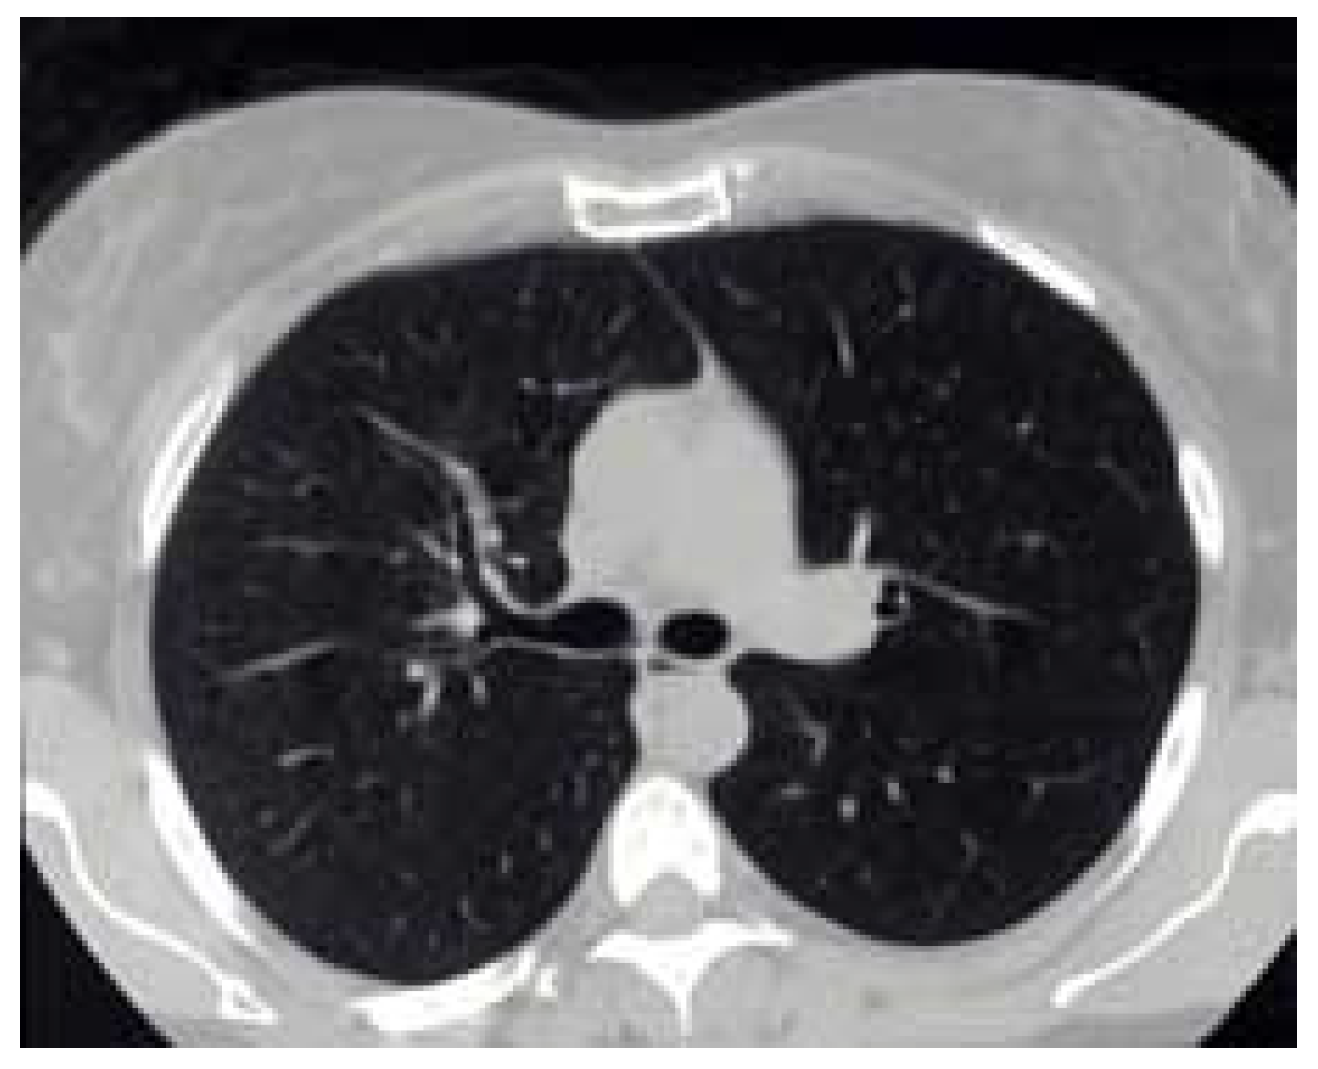

3.4. Medical Image Compression

Figure 24. Original image.